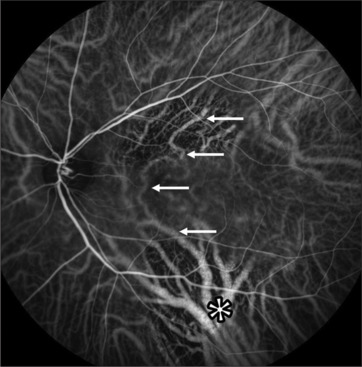

目的:本研究的目的是评估慢性中心性浆液性脉络膜视网膜病变(cCSC)患者的光学相干断层扫描(OCT)和吲吲胺绿血管造影(ICGA)生物标志物作为阈下纳秒激光(NSL)治疗反应的潜在指标。方法:回顾性分析32例NSL术后cCSC患者的36只眼。高缓解(HR)定义为首次NSL治疗后3个月视网膜下液(SRF)完全消退,完全缓解(FR)定义为最后一次NSL治疗后3个月SRF完全消退,所有NSL发作均发生在首次NSL后1年内。生物标志物包括中央黄斑厚度(CMT)、中央凹下脉络膜厚度(SFCT)和漩涡间静脉吻合(IVA)。结果:患者平均年龄54±12岁;86%为男性。基线OCT显示平均CMT为364±130µm, SFCT为292±45µm;ICGA中IVA占64%。HR为50%,FR为78%。较高的IVA率(83%对44%,P = 0.03)预示首次NSL后的不良反应。与没有IVA存在的患者相比,基线时有IVA存在的患者需要一次以上NSL治疗的可能性具有统计学意义(57%对15%,P = 0.02)。结论:OCT和ICGA生物标志物可作为NSL解剖反应的指标。IVA患者在基线时表现出较差的第一反应,可能需要重复激光治疗。

Methods: In this retrospective study, we examined 36 eyes of 32 cCSC patients after NSL. High response (HR) was defined as complete resolution of subretinal fluid (SRF) 3 months after first NSL treatment, full response (FR) as complete resolution of SRF, 3 months after the last NSL, with all NSL sessions occurring within 1 year from the first NSL. Biomarkers included central macular thickness (CMT), subfoveal choroidal thickness (SFCT), and intervortex venous anastomosis (IVA).

Results: Patients were 54 ± 12 years old on average; 86% were male. OCT at baseline showed a mean CMT of 364 ± 130 µm and SFCT of 292 ± 45 µm; 64% showed IVA in ICGA. HR was seen in 50% and FR in 78%. Higher IVA rates (83% vs. 44%, P = 0.03) predicted poor response after the first NSL. Patients with IVA presence at baseline showed a statistically significant higher likelihood of requiring more than one NSL session compared to those without IVA presence (57% vs. 15%, P = 0.02).